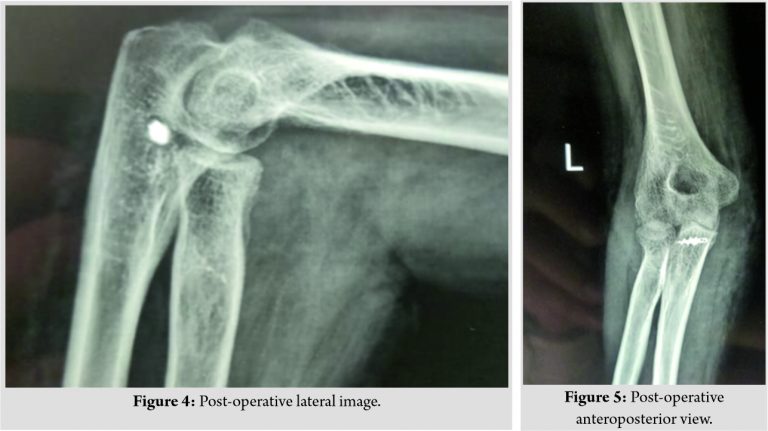

The first step was to identify and preserve the ulnar nerve through a direct medial approach. (Fig. 2) shows the scar site of the medial incision taken. In situ neurolysis of the ulnar nerve was performed between the Osborne fascia and arcade of Struthers. The contacted posterior capsule was excised and the fibrous tissue between the ulnohumeral joint which was blocking the reduction was excised completely, taking care not to damage the cartilage of the joint. Medial collateral ligament (MCL) complex and the flexor mass were found to be completely torn and contracted. Triceps muscle shortening was dealt with complete release and pie-crusting of the muscle subperiosteally. The wound was kept open to allow observation of tension in the ulnar nerve during open reduction and distraction. Next, Kocher’s interval was accessed to enter the lateral part of the joint through a separate lateral incision. (Fig. 3) shows the scar site of the lateral incision through which the Kocher’s interval was accessed. The annular ligament was found to be torn and contracted. The anterior capsule was released and the fibrous tissue was removed. The lateral collateral ligament (LCL) was found to be intact, released subperiosteally, and arthrolysis was done laterally. Open reduction of the elbow joint was done and the elbow stability was assessed. The annular ligament was repaired with triceps fascia (Bell-Tawse procedure) with adequate tension and checked intraoperatively for restriction of pronosupination. MCL was reconstructed with triceps fascia turndown from the medial side and fixed with 2.7mm suture anchors on sublime tubercle after forming a posterior to anterior drill hole tunnel. The sutures along with the fascia were fixed back to the medial epicondyle, thus forming a triangular-shaped stable reconstruction of the MCL. The ulnar nerve was left in cubital tunnel with an adequate cover around it. The post-operative radiographs are shown in (Fig. 4 and 5).

After the medial and lateral reconstruction of the ligaments, the elbow was found to be stable and intraoperative range of motion was checked. Postoperatively, the patient was kept in an above-elbow cast in complete supination for 6 weeks. The patient was regularly followed up and the range of motion was started at the end of 6 weeks. The patient had no instability for daily day to day activities and range of motion was initially from 40 to 100° flexion and from complete supination to 20°pronation. It improved gradually and the patient has 30–140° flexion and complete supination-pronation movements currently at 1 year follow-up. (Fig. 6 and 7) show the patient’s flexion from 30 to 140°.